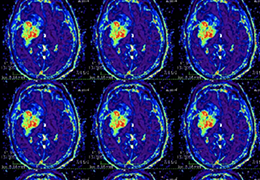

Eclipse 成像智能功能提供强大的处理能力和最佳质量的影像,同时减少质量错误并提高剂量效率。

凭借 AI、专有算法和先进的影像处理能力,提供出色的影像质量和无与伦比的诊断信心。

与标准影像处理相比,智能降噪功能可使客户降低辐射剂量,而不会损失影像质量。这在新生儿和儿科成像中尤其重要,在这种情况下以尽可能低的剂量成像至关重要。